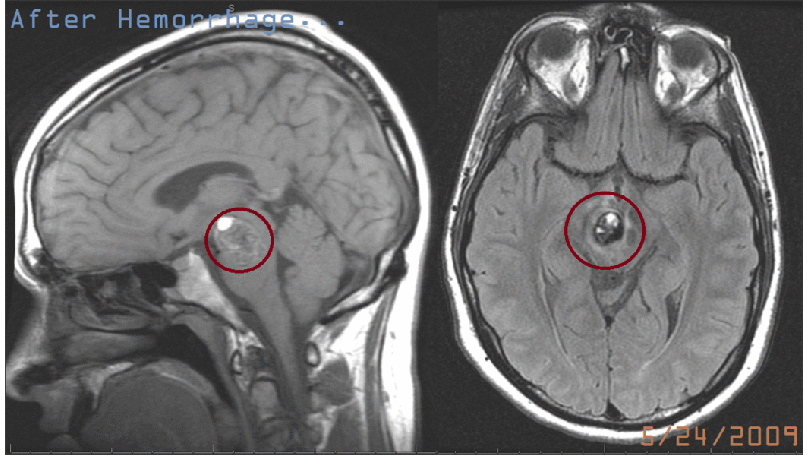

On the last MRI image, notice all the white out has been removed. When looking down from the top of my head, the “cavern” that the cavernous malformation called home is still a dark hole. I can only speculate that this is why I forget stuff almost as quickly as it pops into my head, it gets sucked into this vortex of blackest black, of darkest dark, of ebon opacity, of obsidian obscurity, etc.

This is all to say that my latest scans show no activity, and my recovery continues.